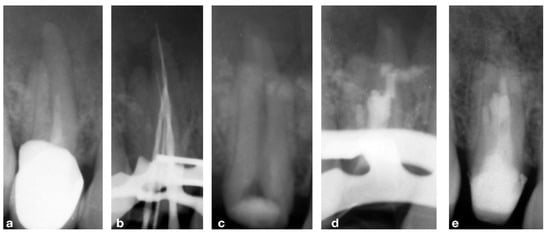

2.1. CASE 1